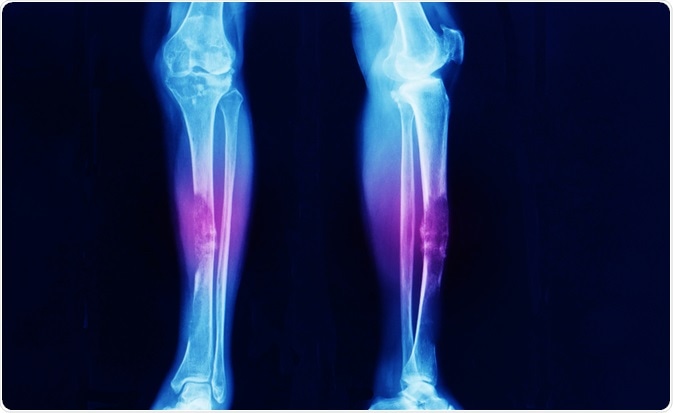

bone cancerImage Credit: Yok_onepiece / Shutterstock.com

Osteosarcoma occurs in the bone cells and most commonly affects the bones in the leg and upper arm. The characteristics of osteosarcoma are similar to spindle cell sarcoma.